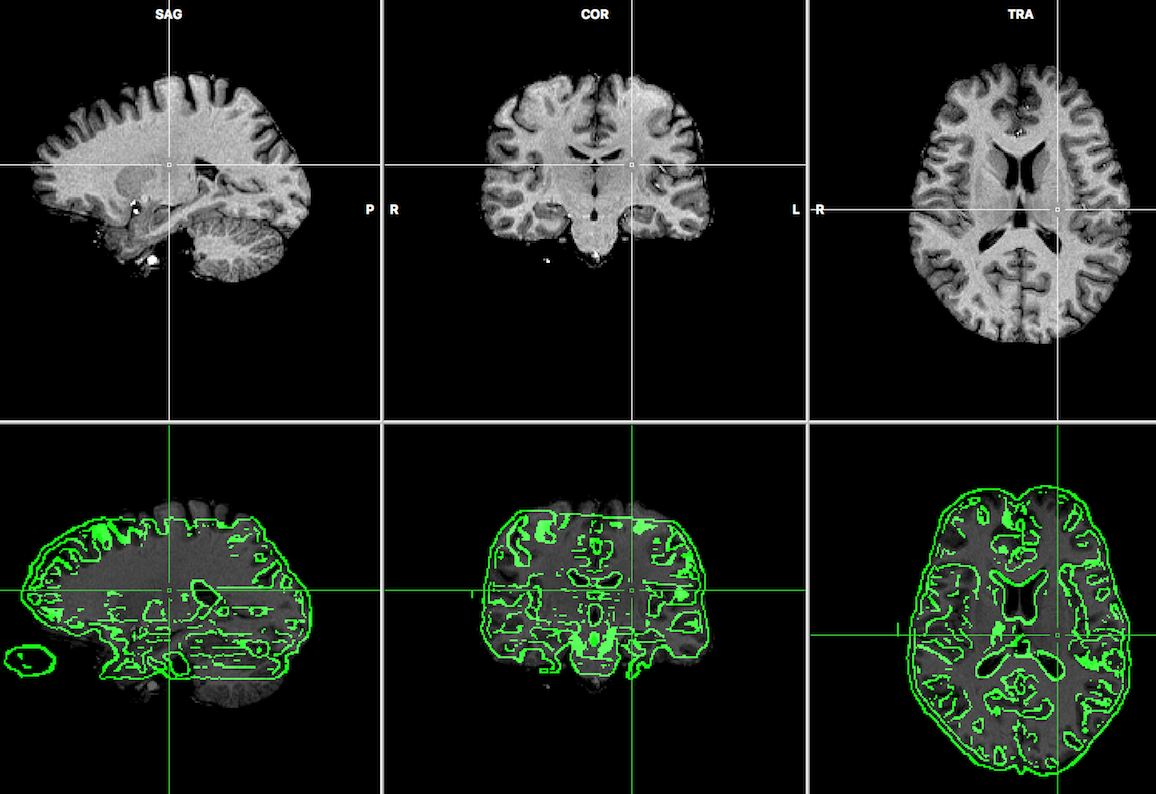

A significant part of my role involved conducting statistical analyses of Positron Emission Tomography (PET) and Diffusion Tensor Imaging (DTI) scans. Using exploratory tools such as MATLAB and Statistical Parametric Mapping (SPM) versions 5, 8, and 12, I analyzed complex DICOM and NIfTI files to uncover patterns between brain region abnormalities.

Additionally, I assisted in the creation of z-score maps, drawing of region of interest (ROI) boundaries, and optimizing the data wrangling pipeline from the initial extraction of imaging data from discs all the way to the final heatmaps.